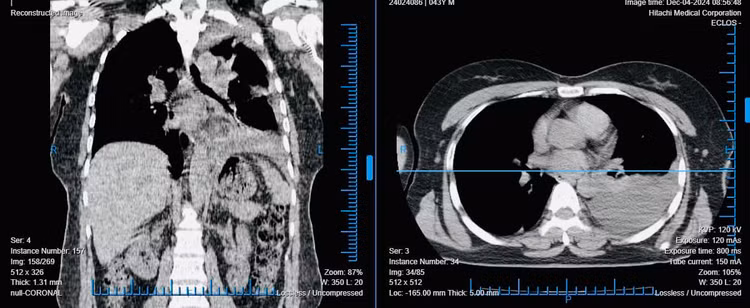

![]() |

| Hình ảnh phổi trước phẫu thuật. Ảnh TTYT huyện Tiên Yên (Phú Thọ) |

Tại đây, chụp cắt lớp lồng ngực cho thấy tình trạng nghiêm trọng: toàn bộ màng phổi trái bị dày dính, với hàng loạt ổ cặn chứa dịch và khí đè nén lên nhu mô phổi, khiến bệnh nhân đối mặt với nguy cơ xẹp phổi nghiêm trọng.